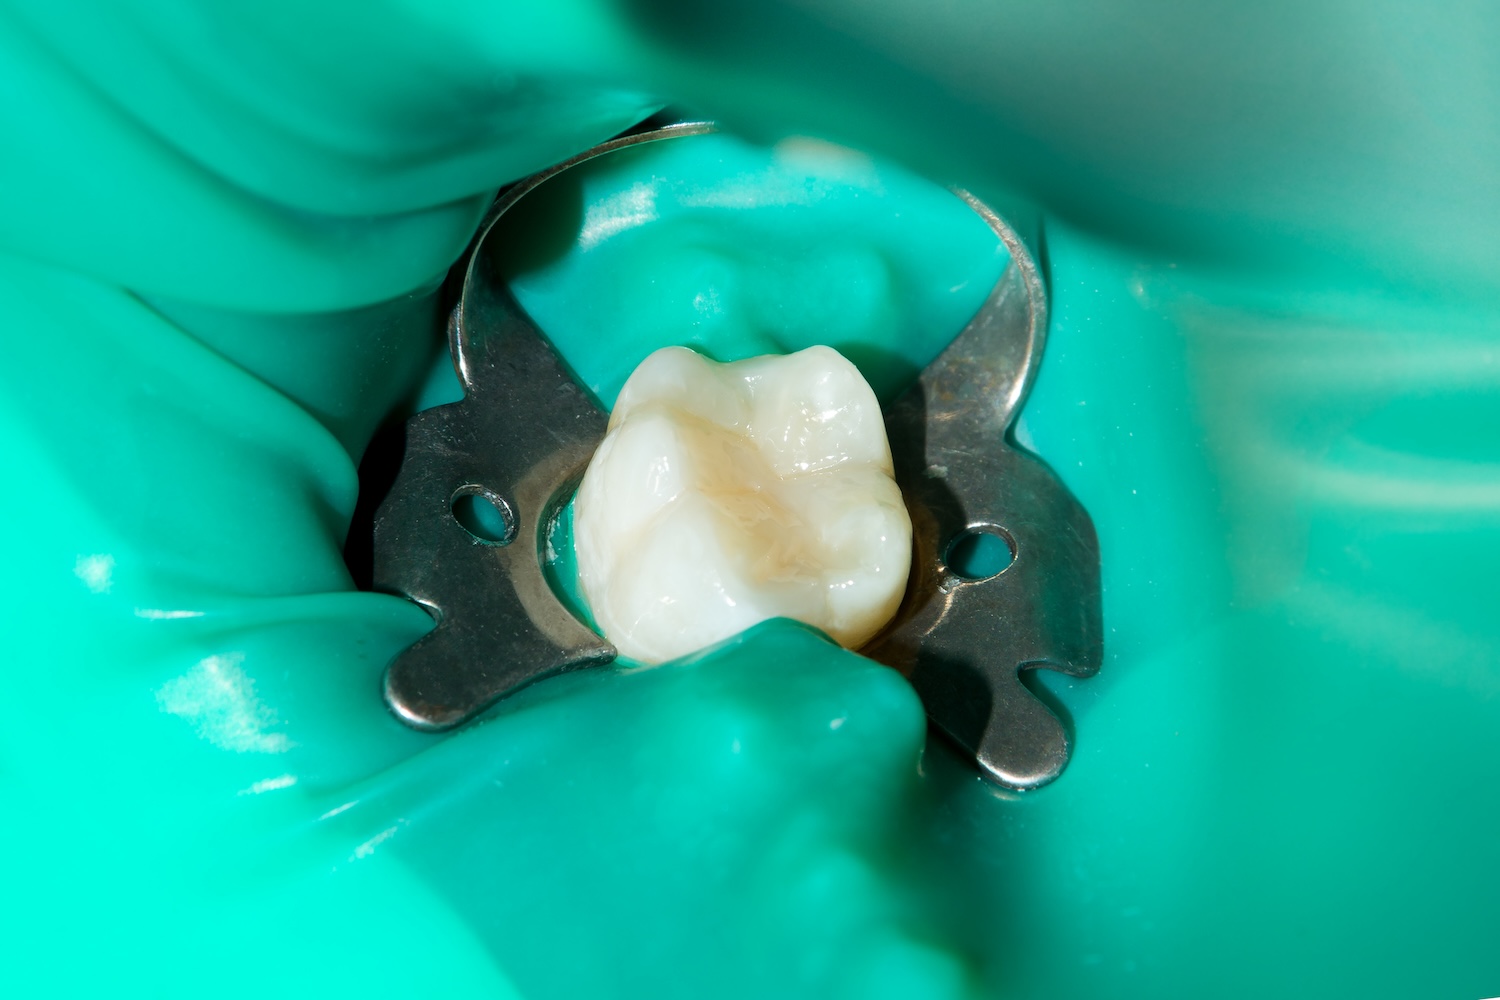

ラバーダム防湿

根管治療は無菌的な環境で行うことが極めて重要です。治療中に患者さんの唾液や口腔内の細菌が根管内に侵入すると、たちまち再感染が起こってしまいます。これを防ぐために、ラバーダム防湿というゴム製のシートで治療部位を唾液から隔離する処置が不可欠です。しかし、この処置は手間がかかるため、日本での健康保険の根管治療で用いている歯科医院は残念ながら少ないです。